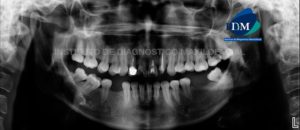

Paciente masculino de 56 años de edad acude al Instituto de Diagnóstico Maxilofacial por molestia en zona molar de lado izquierdo. A la evaluación panorámica